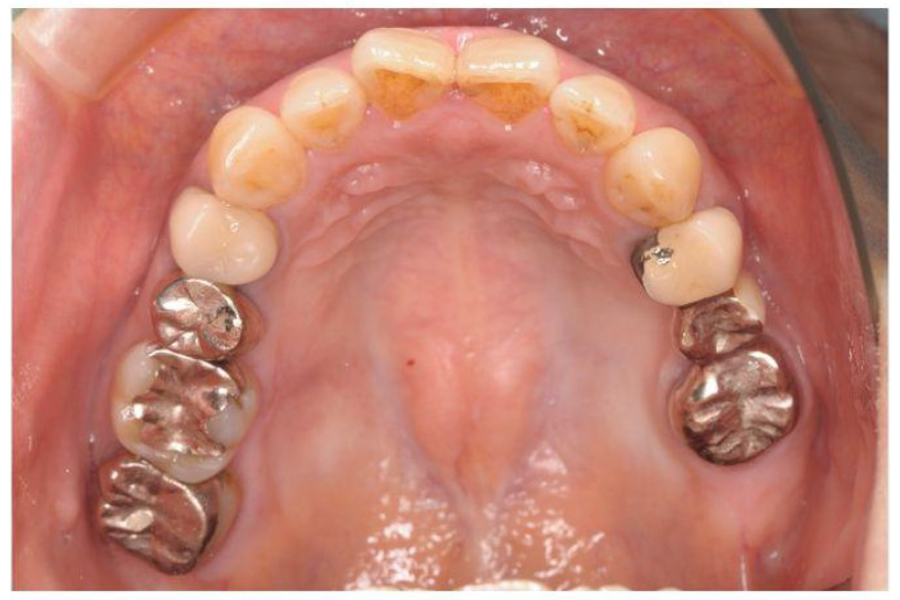

治療前